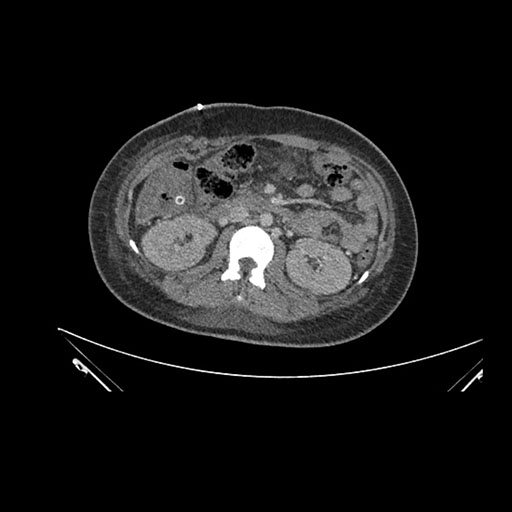

Imaging Analysis

Look through the patient's CT scan to identify any areas of concern for the necessary procedure.

Axial Venous

Based on initial findings, which issue(s) would you be most concerned about?